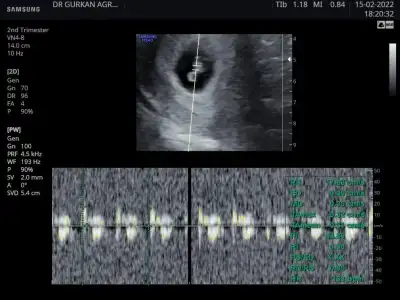

Ben dün akşam gittim bacım kalp atışını duyduk çok şükür rabbim isteyen herkese nasip etsinAynen canım görüntü açısından makina önemliymiş. Doktordan memnun kaldın mı 1 ay sonrasına mi çağırdı artık.

Aynen canım görüntü açısından makina önemliymiş. Doktordan memnun kaldın mı 1 ay sonrasına mi çağırdı artık.

İyice bebek gibi olmaya başladılar maşallahAl canımSana doktor ultrasyon vermedimi fotoğrafını